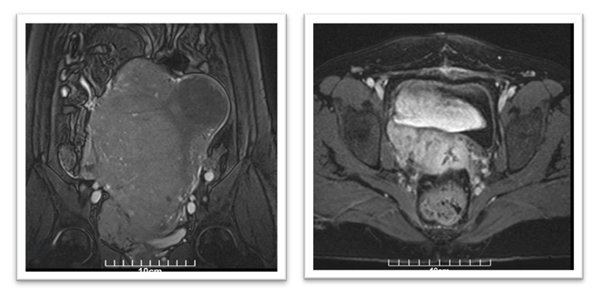

Postoperatively, the patient’s immediate recovery was unremarkable. However, approximately four weeks after surgery, she developed right-sided pelvic discomfort. MRI of the abdomen and pelvis was performed in May 2023 to assess any postoperative complications or residual disease. This imaging revealed a sizable mass in the right pelvic cavity (~8×6×4 cm) in the region of the hysterectomy bed, raising concerns for either local residual tumour or early recurrence. Further evaluation using chest imaging identified multiple bilateral lung nodules (up to 1-2 cm in diameter) that were suspicious for metastatic lesions (Figure 1).

No liver lesions or other distant metastases were seen on abdominal imaging. Based on these findings, the patient was diagnosed with metastatic uterine sarcoma (Stage IV) approximately one month after her initial surgery. To achieve a more accurate assessment of the tumour and expand therapeutic options, ER, PR, AR, Her-2 (Human epidermal growth factor receptor-2), PD-L1 (Programmed Death Ligand-1), and Ki-67 were analysed in the resected tissues.